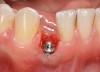

Problem: The implant is placed too facially, and there is significant labial gingival recession, contour change, and mucosal discoloration around the implant, abutment, and crown (Figure 3 and Figure 4). The implant attachment apparatus is intact and healthy, but the patient has a thin periodontal phenotype.

The following case report provides an example of this case scenario: A 28-year-old white female patient presented with her maxillary right lateral incisor significantly longer than the contralateral tooth following restoration of an existing crown that was 10 years old (Figure 3). The patient was dissatisfied with the esthetic appearance of the restoration due to the increased length, recession of the gingival tissues, and discoloration of the surrounding mucosa (Figure 4). Similar to case scenario No. 1, the first step in treatment was to decoronate the healthy implant by placing a flat surgical cover screw and employing a provisional resin-bonded-retained (RBR) prosthesis as a transitional fixed restoration (Figure 5 and Figure 6). The gingival augmentation in situ was allowed to take place for 2 to 3 weeks and was evaluated after that time (Figure 7).

Fig 3. A patient presented with a high smile line and midfacial recession of the maxillary right lateral incisor as evidenced by the increased tooth length compared with the contralateral lateral incisor.

Fig 4. Intraoral view of tooth No. 7 with the gingival zenith more apical than the adjacent central incisor and canine tooth.